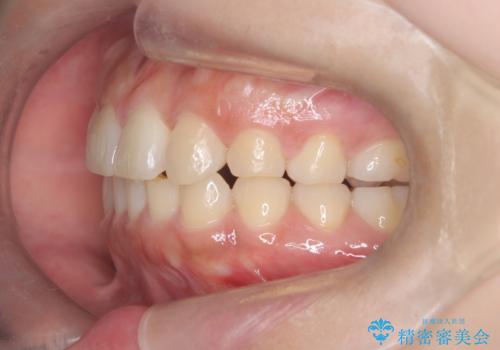

- 「歯の捻じれとがたつき」を主訴に来院された患者様です。

軽度な捻転と叢生だったため、インビザラインのモデレートで治療を行いわずか半年で治療を終える事が出来ました!

目立たないマウスピース矯正【インビザライン】を使用し、

わずか6ヵ月で歯並びがキレイに整いました!